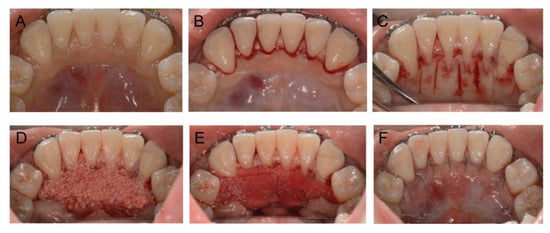

2.4. Treatment Progress